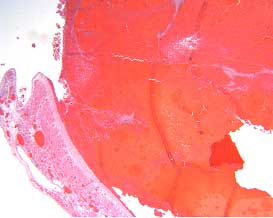

The placental histology of the dividing membrane confirmed a monochorionic diamniotic twin gestation (Figure 3 shows dividing membrane roll with back-to-back amnions and no chorion). There was also a possible acute/recent twin-twin transfusion from Baby “A” to Baby “B” (our patient). The villi from disc “A” were edematous (Figure 4), and those from disc “B” were congested (Figure 5).

Figure 3